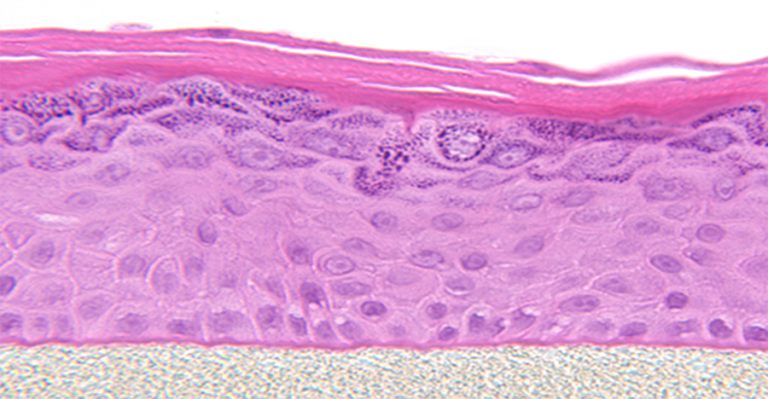

Also known generically as a Reconstructed Human Epidermis (RHE), EpiDerm is a ready-to-use, highly differentiated 3D tissue model consisting of normal, human-derived epidermal keratinocytes (NHEK) cultured on specially prepared tissue culture inserts.

EpiDerm exhibits human epidermal tissue structure and cellular morphology with greater uniformity and reproducibility. It’s 3D structure consisting of organized and proliferative basal cells, spinous and granular layers, and cornified epidermal layers are mitotically and metabolically active.